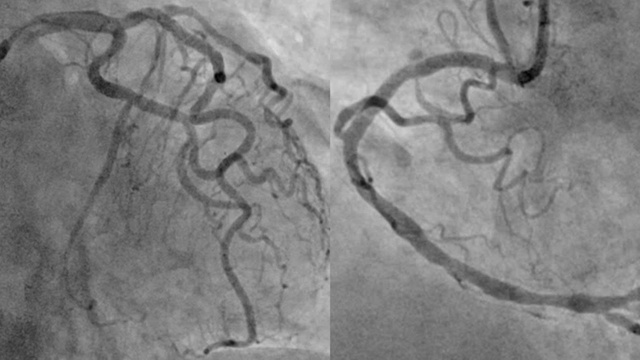

Hình ảnh chụp động mạch vành cho thấy tắc hoàn toàn động mạch mũ (mũi tên đỏ), hẹp nặng cả động mạch liên thất trước (mũi tên vàng) và động mạch vành phải (mũi tên xanh).

Bệnh nhân sau đó được đưa đến phòng DSA để được chụp động mạch vành cấp cứu. Kết quả chụp mạch vành cho thấy tắc hoàn toàn động mạch mũ, hẹp nặng động mạch liên thất trước và vành phải.

Sau hội chẩn, các bác sĩ nhận định: Đây là trường hợp ngưng tim sau nhồi máu cơ tim, với "thủ phạm" là tắc hoàn toàn động mạch mũ, đồng thời hẹp nặng cả hai nhánh động mạch vành còn lại.